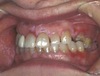

Mom came into the office and said the child had had the first molar extracted before the eruption of the premolar. Based on the following image, what is the likely cause for this discoloration?

Turner hypoplasia